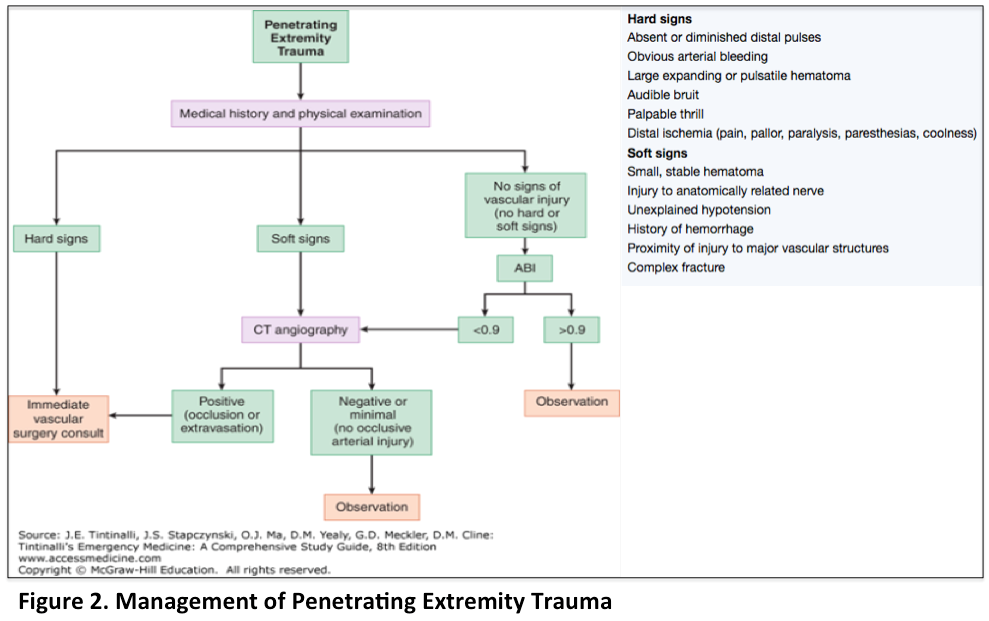

Emdocs Net Emergency Medicine Educationpenetrating Wounds In The